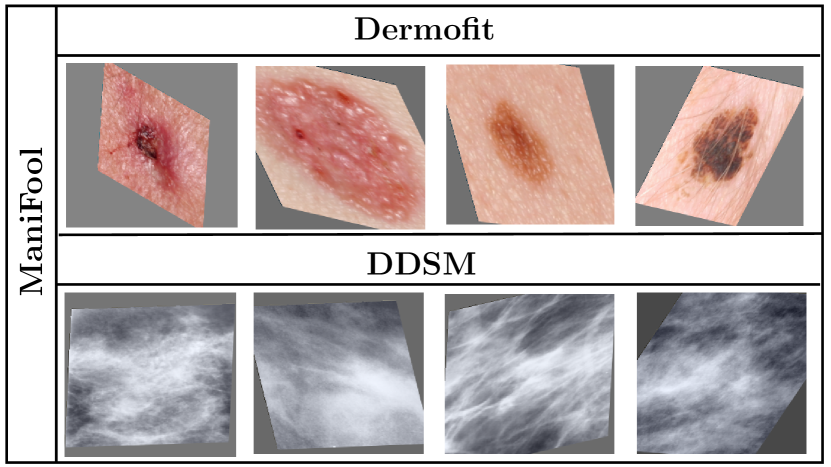

Refer to caption

Figure 2: Examples generated with ManiFool Augmentation for the two datasets, namely Dermofit and DDSM.

Initially, for all the images in the training set of the given dataset, we create ManiFool Augmentation samples that reside around the edges of the class manifolds with an independent black-box classifier f𝑓f. Afterwards, we mix the generated samples with the original data in an equal ratio and train a model from scratch. An alternative approach would have been to utilize all the geometrically transformed images at every step i𝑖i towards the decision boundary for data augmentation. However, it was crucial to maintain an equal ratio of transformed and original samples in the final dataset, so that models utilizing it for training would not be biased to geometrically transformed images, due to an imbalanced amount of samples. Hence, we only utilized the transformed samples in the vicinity of the decision boundary, to provide the maximum possible variance to the models during training. Samples crafted with ManiFool Augmentation are presented in Fig. 2.